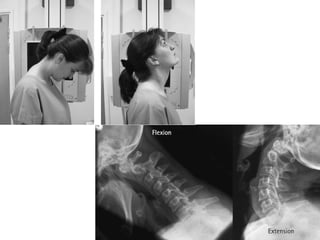

Cervical Spine-Lateral

Position

• Make the patient to stand in front of the x-ray table in true

lateral position.

• Mid saggital plane should be parallel to the center of the

table.

• Depressed the shoulder as much as possible.Ask the patient

to lowered there shoulder as much as possible so as to avoid

overlapping.

• To pull out the patient shoulder more with help of weight

bearing(sand bag) on both hands.

• The chin is raised, so that angle of mandible dose not come in

way to upper c-spine.

• Ensure there is no rotation of the head.

Tube Centering

• Center to the angle of mandible or at the level C4 or at the

level of the upper border of thyroid cardilage.

Cassette centering

• The upper border of the cassette one inch above the EAM.